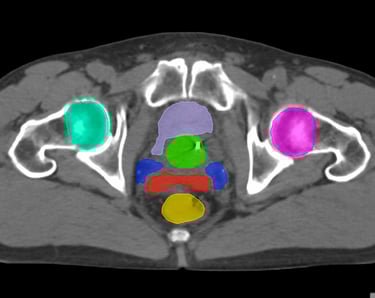

The DAM Contour features a comprehensive collection of OARs and CTVs that are ready for immediate use, without the need for manual creation of atlases or manual adjustment of data. This product includes all standard OAR and CTV structures (over 117 in total).

The Pelvis lymph node region encompasses lymph nodes that include the obturator lymph nodes, internal and external iliac lymph nodes (limited anteriorly at the level of the femoral heads), and extends up to the common iliac lymph nodes, covering the L5/S1 region.

Pelvis